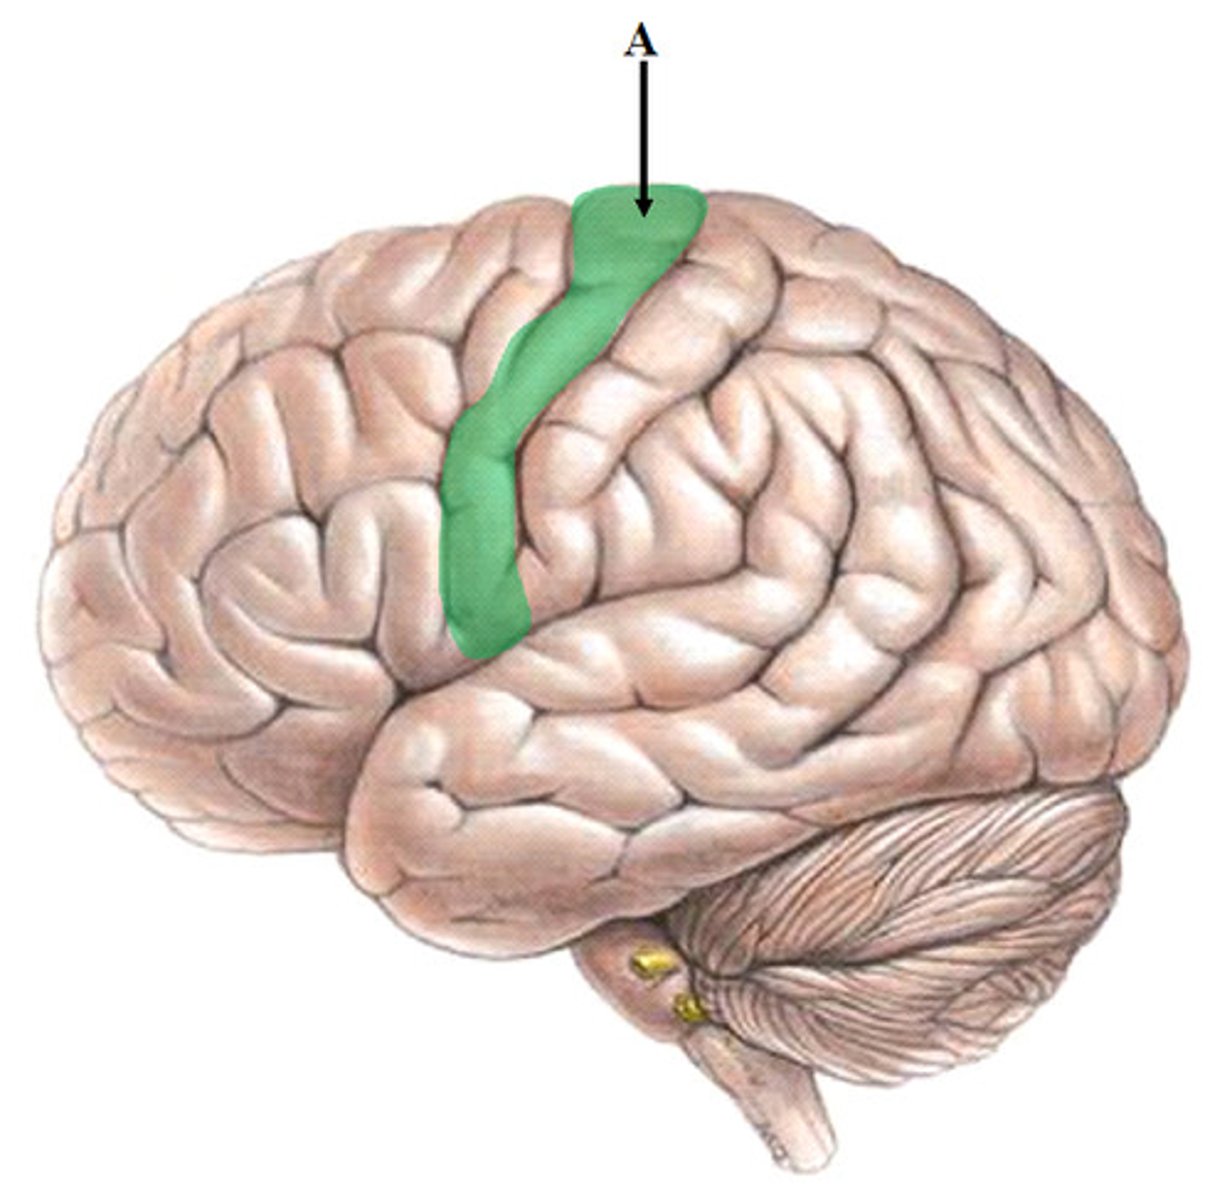

central sulcus

separates frontal and parietal lobes

pre central gyrus

location of primary motor cortex

post central gyrus

primary somatosensory cortex